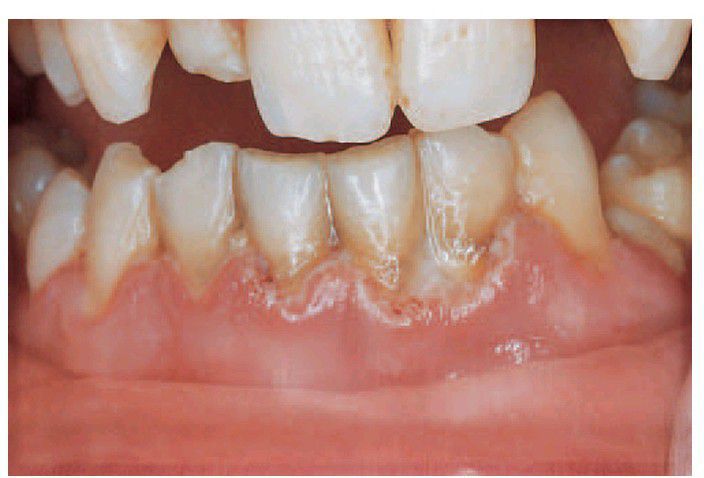

Acute necrotising ulcerative gingivitis

. The characteristic features of the lesion, the crater-shaped ulcers starting at the tips of the interdental papillae, are covered by a slough, as shown here.